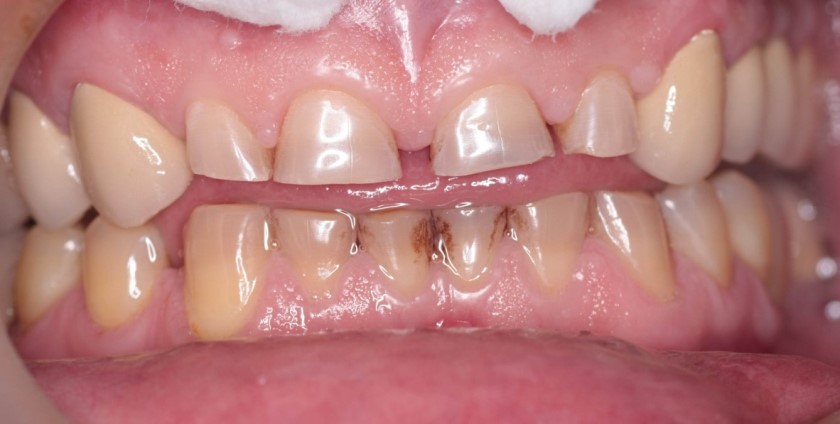

Фото

Патологическая стираемость зубов — актуальная проблема для стоматологов и пациентов. Многие замечают, что с возрастом зубы становятся чувствительными, и привычные продукты вызывают дискомфорт. Люди отказываются от кислых и жестких блюд, чтобы не усугублять ситуацию. В социальных сетях обсуждаются методы профилактики, включая специализированные зубные пасты и регулярные визиты к стоматологу.